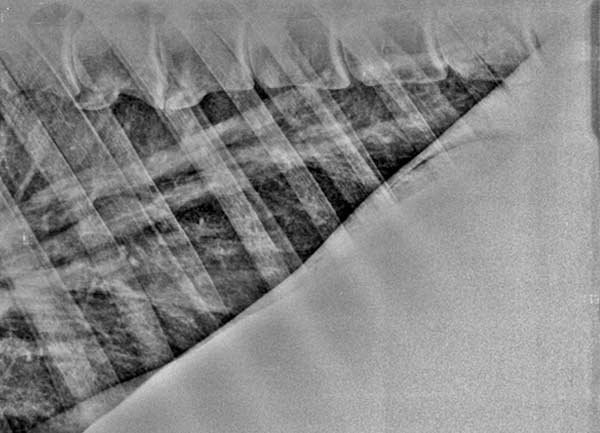

Röntgenfoto van longen van een paard met ernstige longproblemen: de luchtwegen zijn reeds "verlittekend".